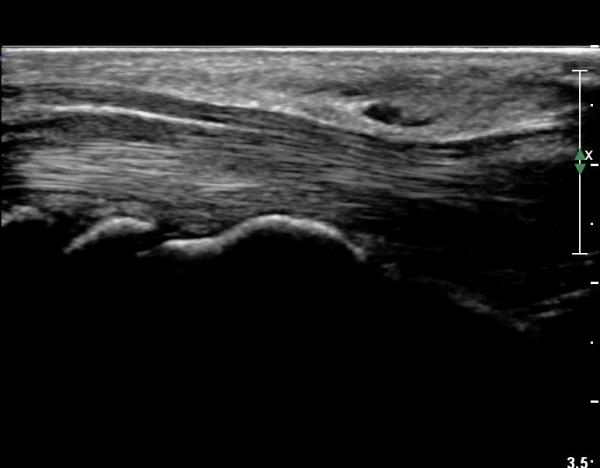

¾Æ·§ÆÈ ¸»´ÜºÎ Ⱦ´Ü¸é°Ë»ç¿¡¼­ ¼Õ°¡¶ô ±¼°î ÈûÁÙÀÇ ºñÈÄ¿Í ÈûÁÙ ½ÉºÎ¿¡ ¼ö¾×Àú·ù°¡ °üÂûµÈ´Ù(»çÁø 1).